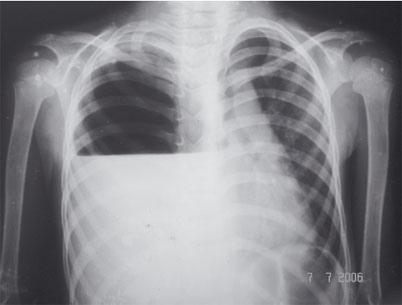

Hidropneumotórax

Figura 53.1: Hidropneumotórax.